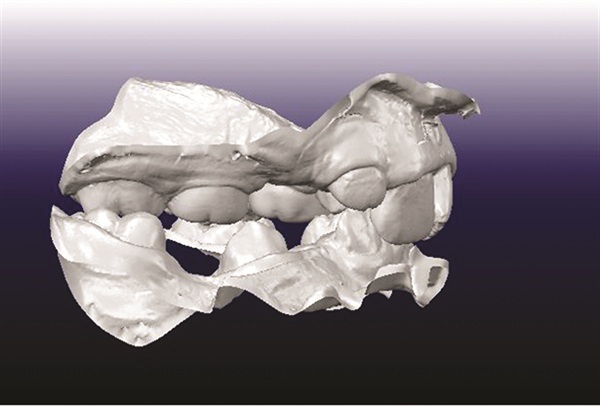

A 12-year-old male presented with severe Class II, deep bite, and significant crowding. The original poster was torn between two conflicting clinical pictures. Half the diagnostic findings pointed toward extraction: second molars impacted in the ramus, a blocked lower left canine, blocked maxillary canines, and a nearly full-step Class II relationship. The other half suggested non-extraction with vertical control to avoid deepening the bite further. The concern was that by the time crowding was resolved and the deep bite corrected, the incisors would be too flared for effective Class II correction without further proclination. The question posed to the forum was whether immediate upper first premolar and lower second premolar extractions were the best route forward (Figs. 1–11).

Before treatment planning could advance, multiple members flagged the need for better diagnostic records. The buccal photographs were not diagnostic, making it difficult to assess the true occlusal relationship. A severe transverse discrepancy was evident, along with possible soft tissue or skeletal asymmetry and potential maxillary cant. One clinician recommended obtaining a cone beam computed tomography scan to properly evaluate the asymmetry before finalizing any treatment plan. Another emphasized the importance of retraining staff on proper photo protocols to avoid similar issues in future cases. The original poster acknowledged the feedback and posted updated images.

The most frequently suggested treatment involved rapid palatal expansion followed by a Herbst appliance. Several clinicians viewed this as an ideal growth modification case given the patient’s age, low mandibular plane angle, and Class II presentation. Expansion would address the transverse deficiency first, with Herbst therapy used to advance the mandible and distalize the maxillary segment while creating space for the blocked canines. Because the lower incisors were upright and the patient exhibited a low-angle pattern, contributors felt the lower arch could tolerate some proclination. Opinions varied on lower appliance design, with some recommending premolar crowns and lingual arch support to help manage canine alignment while minimizing unwanted incisor effects.

One contributor emphasized that this was not a surgical case and argued that fixed functional therapy offered a predictable approach through tooth movement. They viewed a Herbst as the most predictable way to distalize upper molars while acknowledging that the panoramic radiograph showed evidence of posterior mandibular crowding. Depending on the severity of that crowding, either upper first premolar and lower second premolar extractions or Herbst therapy could yield good results.